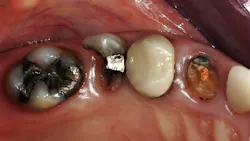

- Tooth characteristics: According to research at Clinicians Report Foundation, when about one-half of the coronal portion of the tooth is missing, it needs a retentive buildup for optimum strength and restoration retention (figures 1 and 2). It is best if root canal treatment is not necessary. Other characteristics: no serious periodontal disease, and the tooth has normal stability. These characteristics are optimum.

- Seat crown, preferably with resin-modified glass ionomer: RelyX Luting, FujiCEM Evolve, etc. (figures 3 and 4)